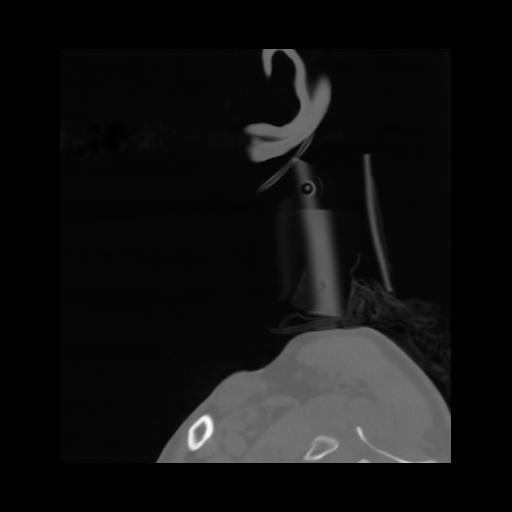

14 P.BLANDAS,,Sagittal,2.000,P.BLANDAS,Sagittal,